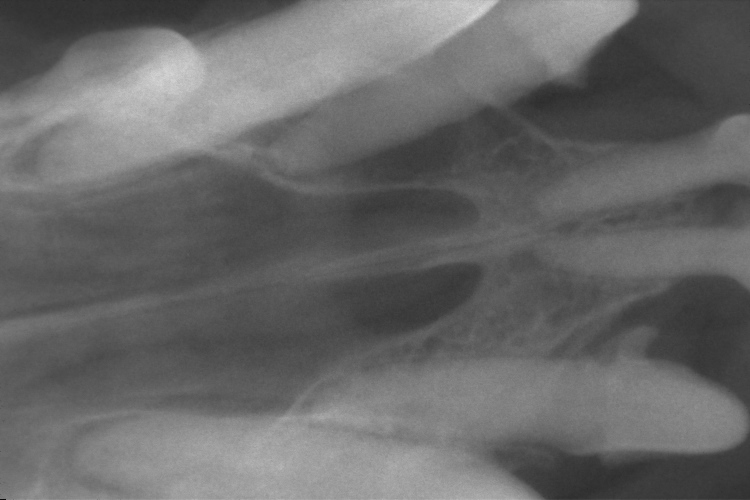

歯科レントゲン

上顎切歯のレントゲンです。

ぐらつきのあった右上顎第3切歯の歯槽骨が吸収し、黒く抜けているのが確認できます。

(黄色斜線部分の歯槽骨が溶けてなくなってしまっています。)